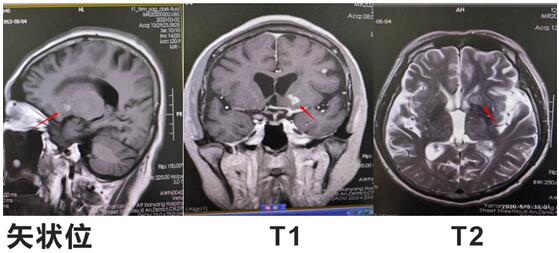

患者邱某,男,67岁 ,因“反复低热头痛40余天”入住我院神经内科三病区,入院后行神经系统体格检查示:表情淡漠,脑膜刺激征阳性;行颅脑磁共振增强扫描示:颅内可见多发点状及小片状结节灶,增强扫描呈小片状及环形明显强化,考虑①感染性病变,结核性脑膜炎可能,②转移瘤待排:请结合临床实验室检查;行腰椎穿刺术示:颅内压310mmH2O,潘氏试验阳性,并于脑脊液中检测出结核分枝杆菌(咸阳市首例)。脑脊液常规:淡黄色清亮,白细胞计数 210*106/L,潘氏试验阳性,中性粒细胞比率 90.0%。脑脊液生化:葡萄糖 1.40mmoI/L,氯 105.5mmol/L,微量总蛋白 2749mg/L,陈萍主任医师、代昌飞副主任医师及科室其他医师慎重讨论后考虑:结核性脑膜炎,并立即制定抗结核、降低颅内压、抑制脑水肿、减轻炎症反应等相关治疗方案。王宝艳护士长指导护理应加强护理,早期康复。经讨论汇总,为该患者制定特色治疗方案,动态调整,密切观察。在科室医生护士的精诚协作下,患者渡过险关。复查腰椎穿刺术:初压:170mmH20,常规:潘氏试验阳性;白细胞计数 120*106/L。淋巴细胞百分率 10.0%,中性粒细胞百分率 90.0%。生化:微量总蛋白 1503mg/L。出院后继续抗结核治疗。